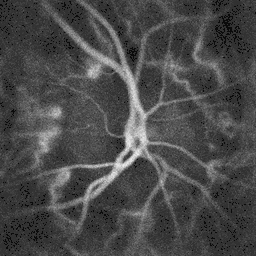

Blood flow in the retina and choroid in the optic disc region can be revealed non invasively by near-infrared laser Doppler imaging.[4] Laser Doppler imaging can enable mapping of the local arterial resistivity index, and the possibility to perform unambiguous identification of retinal arteries and veins on the basis of their systole-diastole variations, and reveal ocular hemodynamics in human eyes.[5] Furthermore, the Doppler spectrum asymmetry reveals the local direction of blood flow with respect to the optical axis. This directional information is overlaid on standard grayscale blood flow images to depict flow in the central artery and vein.[6]